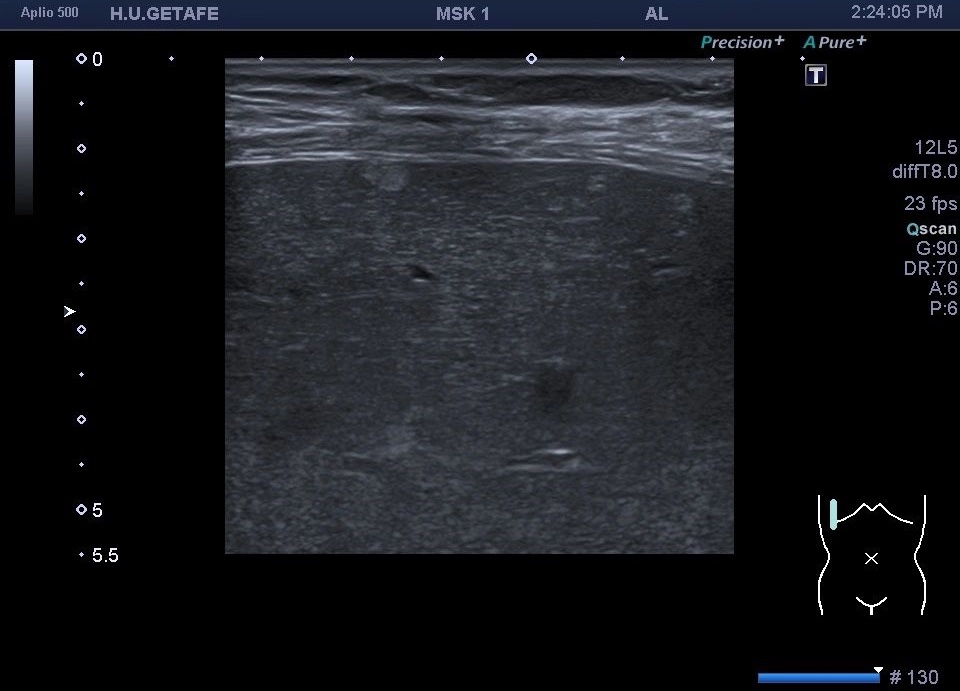

Pero en esta ocasión te quiero mostrar una cosa muy a tener en cuenta. En este caso es un estudio muscular dorsal y como hallazgo casual encontramos un montón de micro hemangiomas todos menores de 5 mm y que se hacen visibles por el uso de la sonda lineal de alta frecuencia.

Enseñanza: Que el árbol no te impida ver el bosque.